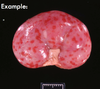

What are the molecular and morphologic changes of the image? ( MDx)

Clinical history and signs: 3 week old puppy, anorexia, dypsnea, abd pain upon palpation, normal rectal temperature

Multifocal, acute renal necrosis and hemorrhage or necrohemorrhagic nephritis

What is the etiology?

Clinical history and signs: 3 week old puppy, anorexia, dypsnea, abd pain upon palpation, normal rectal temperature

Canine herpesvirus-1 (CHV-1)

- red spots are from the virus targeting endothelium

What is the pathogenesis?

Clinical history and signs: 3 week old puppy, anorexia, dypsnea, abd pain upon palpation, normal rectal temperature

Transmission CHV-1 to pup at birth >incubation period of up to 1 week > virus replicates at temperature lower than 37C (98.6F) > endothelial cell tropism > multifocal necrosis in numerous organs